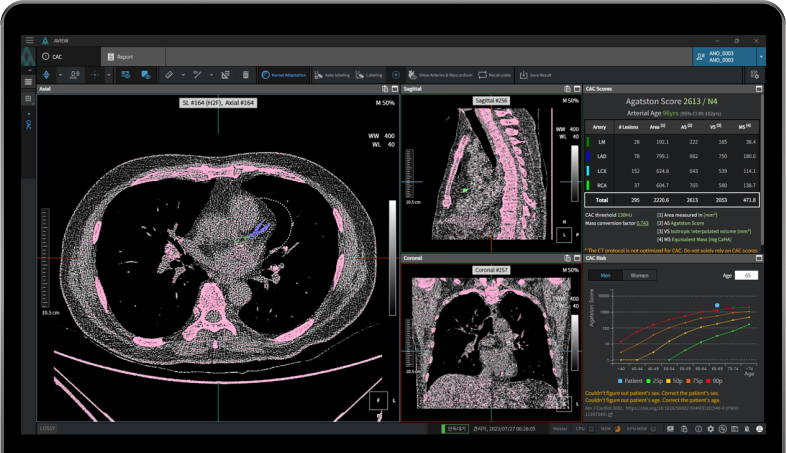

- CT 스캔: 관상동맥 석회화의 상태를 명확하게 볼 수 있는 비침습적인 검사 방법으로, 좌우 심장관의 석회화 수준을 확인할 수 있습니다. 많은 경우, 이 검사는 영화 한 편 보는 시간 안에 가능하여 매우 효율적입니다.